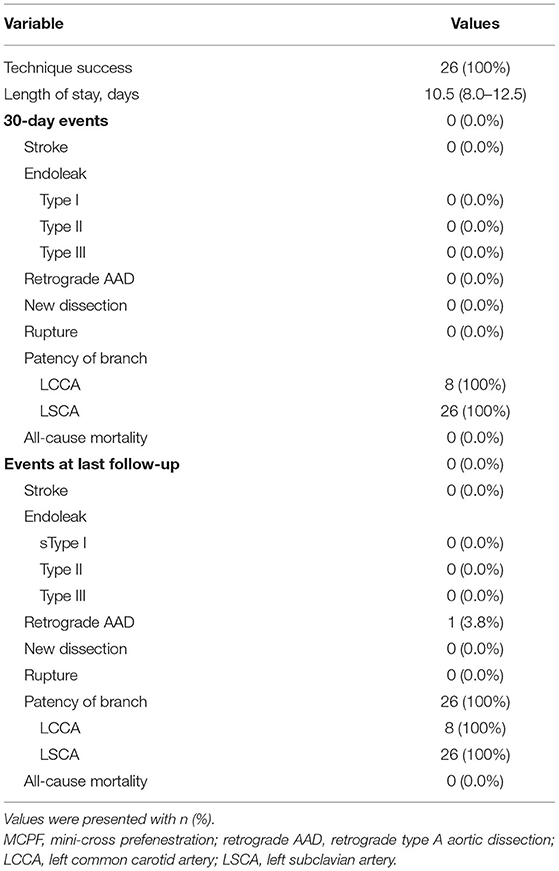

After general anesthesia, the left femoral artery and left brachial artery were exposed, cannulated with a 24-Fr sheath and an 8-Fr sheath separately. Through the access of the femoral artery, the digital subtraction angiography (DSA) was made by a pigtail catheter (Figure 3A). The location of prefenestration was determined by preoperative CT angiography (CTA) and intraoperative aortography. The prefenestrations were made on Valiant Captivia Stent Grafts with a 5 × 5 mm cross (Supplementary Movie 1). The range of oversizing rate was 5 to 20% according to the experience of operators. Before the stent graft was reloaded into a delivery system, the tip of a guidewire (RF*GA35153M, Terumo, Japan) was induced through the fenestration for the purpose of traction from the aorta to the LSCA (Supplementary Movie 2). After preparation, the traction guidewire was induced from femoral access and caught from the brachial access (Figure 3B, white arrows). Then, a peripheral angioplasty balloon catheter (Mustang, Boston Scientific, Natick, Massachusetts, USA) was induced through the guidewire in order to (1) prevent the cutting effect on the LSCA and (2) prepare for revascularization of the LSCA (Figures 3B,C, yellow arrows). When the stent graft was induced beneath the LSCA, multiple observation perspectives from DSA were adjusted to prove the traction guidewire was not twisted. The key step then was performed by one operator and two helpers. The operator controlled the delivery system and released the main stent graft; helper no.1 controlled the super stiff guidewire and helper no. 2 controlled the traction guidewire to make sure that they were in place (Figure 3C). After the release of the main stent graft, the fenestration was softly enlarged by the balloon at 6–8 atmospheres (Figure 3D) and the Fluency Plus Stent Graft was directly induced through brachial access and again flared by a peripheral angioplasty balloon at 8–10 atmospheres (Figure 3E). The branch stents were 10–20% oversized to the LSCA. When there was a need to cover LCCA for a sufficient landing zone, additional LCCA access was exposed for a traction guidewire. The choice of LCCA branch stents was according to the preference of operators, in which there were Viabahn (Gore, Flagstaff, Arizona, USA) and LifeStent (Bard Peripheral Vascular, Germany, UK) devices. The definition of technical success was the successful implantation of main and branch stents without any type I/III endoleak, migration (Figure 3F), or any other immediate major adverse cardiac and cerebrovascular events (MACCE).

Figure 3. Fluoroscopic demonstration of the fenestrated stent graft delivery and engagement. (A) Morphological feature of aortic dissection through the digital subtraction angiography. (B) Delivery and advancing of the main stent graft into the proper landing zone. A traction guidewire was established through the left subclavian artery (LSCA) (white arrows). An angioplasty balloon catheter was prepared for the expansion of the fenestration (yellow arrows). (C) The main stent graft was released and the LSCA was temporarily covered. The traction guidewire was still in the stent graft (blue arrow). (D) Angioplasty of the LSCA through the guidewire from left brachial access (green arrows). The duration from coverage of the LSCA and revascularization was 36 s (red arrows, 14:14:34–14:15:10). (E) Deployment and engagement of the LSCA branch stent graft. (F) Final aortogram demonstrating patent arch branches and exclusion of the false lumen.

First, the location of the fenestration was confirmed by the traction guidewire (Figure 3B), which simultaneously reduced the endovascular procedure time and risk of dislocation between the branch artery and fenestration. This design was inspired from the construction of single-branched Castor stent graft, which is confirmed to be effective and safe for aortic arch pathologies (20). The guidewire preloaded in the main stent graft could help the operator to easily place the stent graft in the designed location (Figure 3B, white arrows). In the previous study, a radiopaque marker was always needed for the right implantation of stent grafts (21). However, plenty of time used for markers increased the burden of patients. According to the previous studies about handmade fenestration for the LSCA, the mean operation time was 171–176 min, which was significantly longer than our data (mean operation time, 125 min) (22, 23).

Second, the revascularization of the LSCA/LCCA was literally rapid around 60 s in this study (Figure 3D; Table 2). Given the importance of supra-arch vessels, the rapid LSCA/LCCA revascularization is demanding study (24). In this study, the prefenestration had a 5 × 5 mm hole, which allowed the blood flow to come through. More importantly, when a main stent graft was implanted, the balloon was already prepared for rapid revascularization (Figure 3C). Although the traditional fenestration technique does not need to consider the time of revascularization, unsuitable fenestration may cause unexpected coverage or endoleak (25). In terms of the in-situ fenestration technique, it takes time to penetrate the main stent grafts, which may increase the risk of cerebral infarction (24, 26).